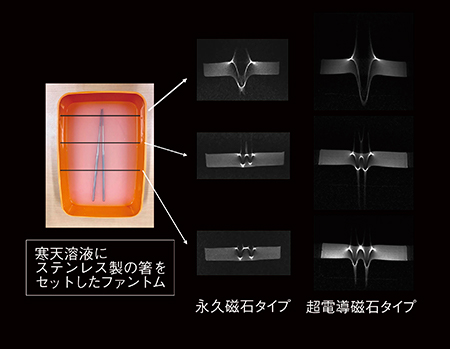

5.金属の影響のある撮像(図5)

金属の影響も静磁場強度が高くなるほど強くなるため,超電導磁石タイプでは金属アーチファクト抑制に特別なシーケンスが開発されています。ただし,出血巣の場合は,血液中の金属である鉄成分を描出しているため,低い静磁場で描出能を改善するには,T2*強調度を高くする,スライス厚を薄くするなどパラメータの調整が必要になります。

図5 金属画像の違い